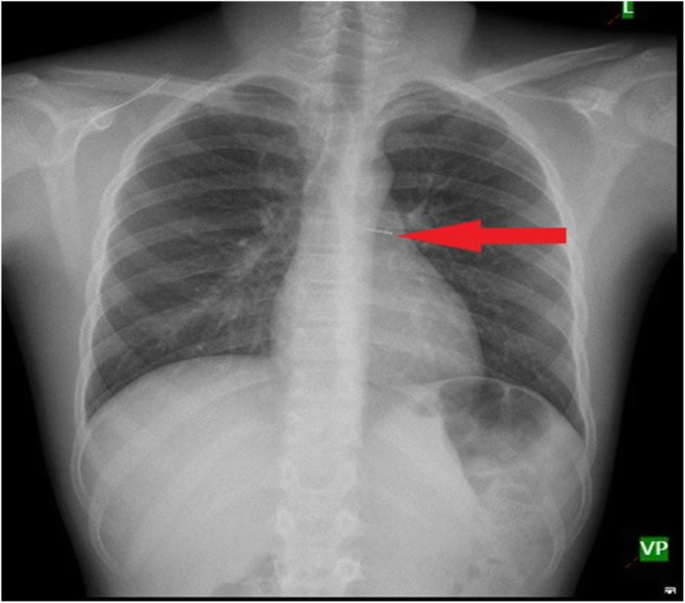

Unlike adults, toddlers do not have clear recall of FBA, thus the diagnosis is most often dependent on the mother’s history, clinical findings such as onset and duration of symptoms and suspicion. Chest x -ray is the most common investigation done in these cases and majority of the time chest- x rays are normal (Fig. 4).

The typical findings on chest radiograph which is diagnostic is unilateral lung hyperinflation, collapse, consolidation of one lung and mediastinal shift. Many authors in their study have reported percentage of normal chest X -ray around 20–42% [7, 8]. In our study normal chest x-ray was found in 39% of patients. Normal chest X-ray is accepted in early phase as most aspirated foreign bodies are vegetative in nature and cannot be seen on chest x ray.

Later, when the organic substance swells with inflammation it occludes the bronchus completely and typical chest x-ray findings appear (Fig. 5).